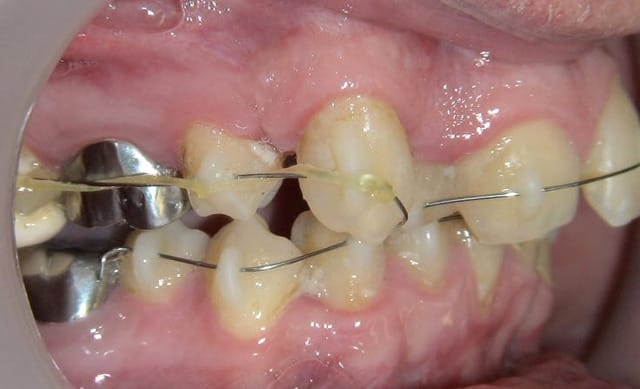

Ca y est ... mes 3 premiers cas de Dancha en pré implantaire.

Je sais je vais me faire lapider et critiquer mais c'est bien pour ca que je vous montre ces 3 cas.

je suis ouvert à toutes critiques à partir du moment où elles sont contructives ;-))

Olivier